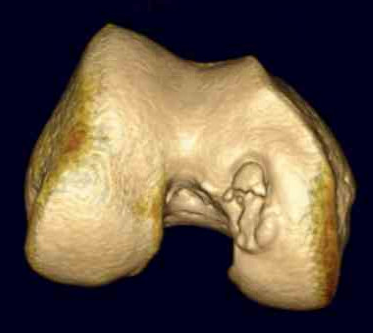

CT

Osteochondral defect